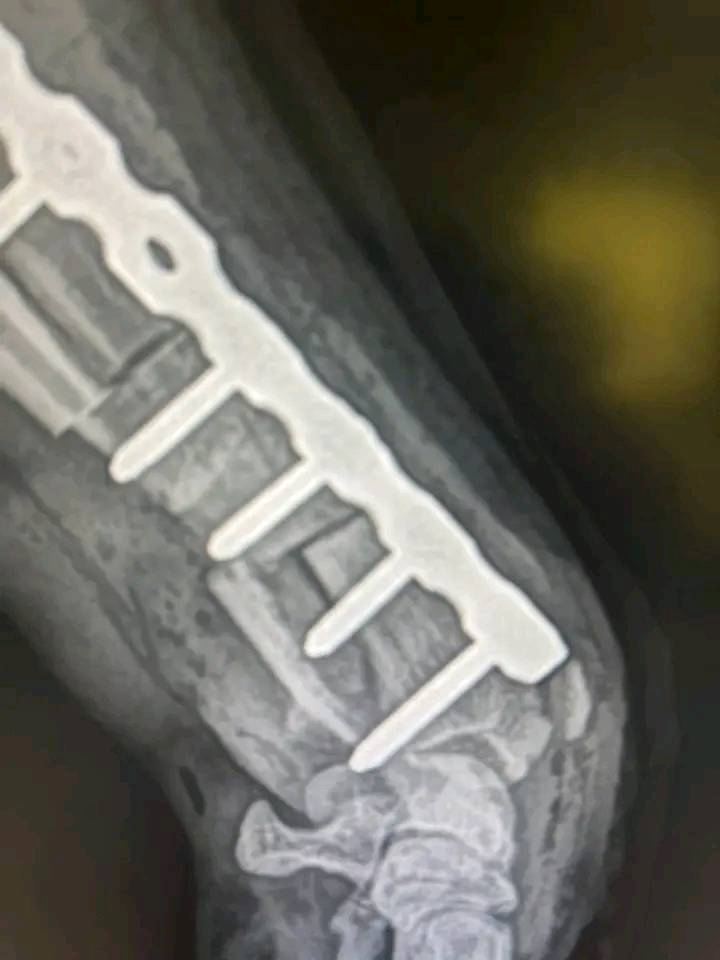

Die Bilder (von mir anonymisiert)

- Der Hund auf den Bildern heißt Martin, ist ein Rottweiler und wird von Karin Hohenberger versorgt.